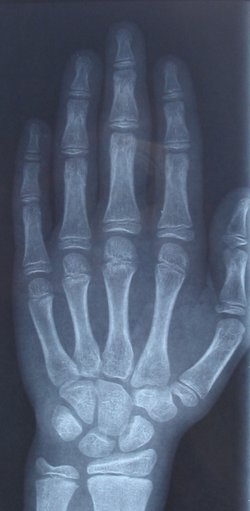

أشعة إكس توضح عظام يد الإنسان.

Illustration depicting the bones of the human hand